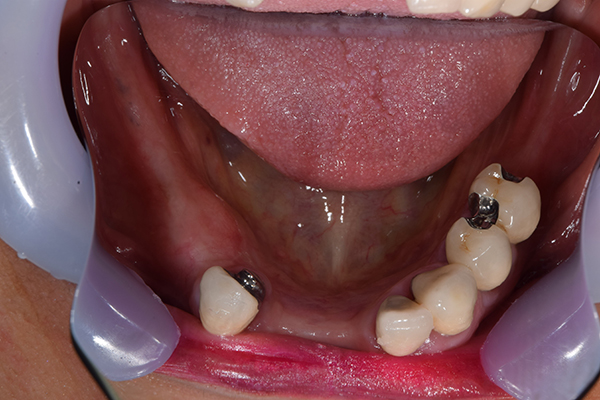

下の入れ歯

前歯が折れて当院にいらっしゃいました。 過去に下の入れ歯を作ったが、合わなくなってずっと入れ歯をいれていらっしゃらない患者様でした。 これは奥歯で噛むことができないため、前歯で噛むことを繰り返したために、負担に耐えられなくなった前歯が折れてかぶせ物ごと 外れてしまったのだと考えられます。 痛くない、違和感の少ない、下の入れ歯を作ることがこの方のゴールであると考えられました。

上下の入れ歯が外れやすくなったということでいらっしゃいました。 顎の骨はしっかりしていましたので、精密な型取りさえすればしっかりした入れ歯がつくれると思いました。 また下には6本歯が残っていましたが、虫歯になっている歯もありました。 かぶせ物のなかで大きな虫歯があった歯があり、1本だけ残せない状態でした。

上の入れ歯は確かに吸着は甘くなっていました。 また下の入れ歯はバネの一部が壊れており、安定感がなくなっていました。